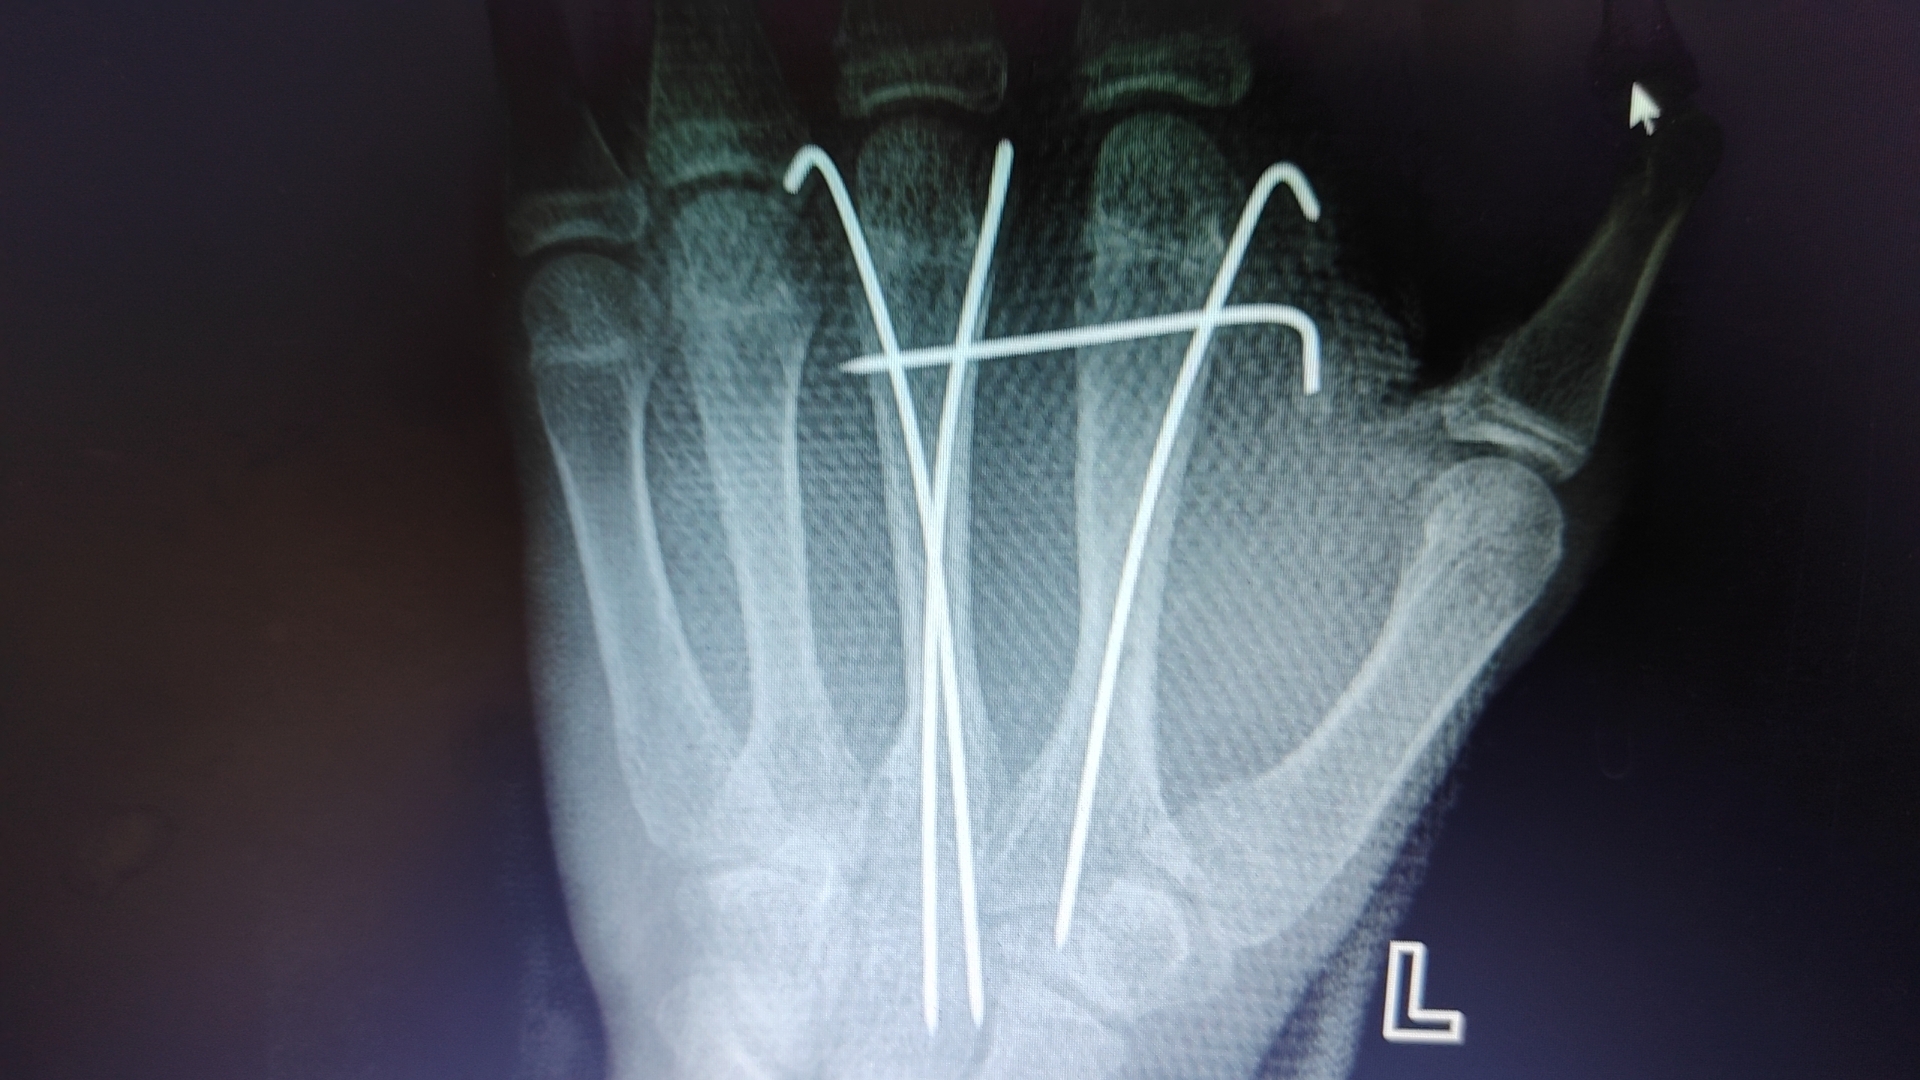

大家好!我是你們的骨科醫(yī)生,今天我非常榮幸能在這里為大家?guī)硪恍╆P(guān)于骨骼健康的小知識。首先,讓我們了解一下骨骼的重要性。人體的骨骼系統(tǒng)由206塊骨頭組成,它們支撐著我們的身體,保護(hù)著重要的器官,并且使我們能夠進(jìn)行各種各樣的活動。然而,隨著年齡的增長以及不良的生活習(xí)慣,我們的骨骼可能會出現(xiàn)各種問題,如骨折、骨質(zhì)疏松、關(guān)節(jié)炎等。因此,保持骨骼健康對我們來說至關(guān)重要。那么,我們應(yīng)該如何保護(hù)我們的骨骼呢?以下是一些建議:1.均衡飲食:確保攝入足夠的鈣和維生素D。鈣是構(gòu)成骨骼的主要成分,而維生素D有助于身體吸收鈣。富含鈣的食物包括牛奶、奶酪、酸奶等乳制品,以及綠葉蔬菜如菠菜和甘藍(lán)。維生素D則可以通過曬太陽或食用魚類、蛋黃等食物來獲取。2.適度運動:負(fù)重運動可以幫助增強骨骼,提高骨密度。如快走、跑步、跳繩、跳舞等。此外,力量訓(xùn)練也有助于增加肌肉力量,從而減輕對骨骼的壓力。3.戒煙限酒:吸煙和過量飲酒都會影響骨骼健康,增加骨折的風(fēng)險。為了您的骨骼健康,請盡量戒煙并限制酒精攝入。4.預(yù)防跌倒:隨著年齡的增長,跌倒可能導(dǎo)致嚴(yán)重的骨折。為了預(yù)防跌倒,請確保家中環(huán)境安全,避免在濕滑的地面上行走,穿著合適的鞋子,并定期檢查視力。5.定期體檢:定期進(jìn)行骨密度檢測和其他相關(guān)檢查,以便及時發(fā)現(xiàn)潛在的骨骼問題。最后,我想提醒大家,骨骼健康是我們生活質(zhì)量的重要保障。希望大家能夠重視骨骼健康,養(yǎng)成良好的生活習(xí)慣,讓我們的骨骼更加強壯,為我們的生活增添更多精彩!如果您有任何關(guān)于骨骼健康的問題,歡迎隨時咨詢我。祝大家身體健康,生活愉快!此致敬禮您的骨科醫(yī)生